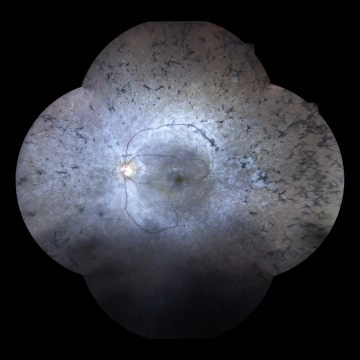

Retinal diseases may be inherited or acquired disorders. They can affect the young and old. Eg. Diabetic Retinopathy, Retinal Detachment, Retinal Vascular Occlusions, Age Related Macular Degeneration, Retinitis Pigmentosa, Retinopathy Of Prematurity and Retinoblastoma ( Cancer of the retina) etc.